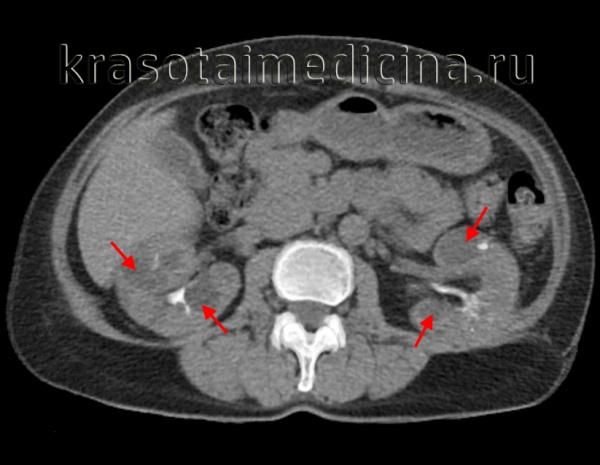

(Слева) КТ без контрастирования, аксиальная проекция: поликистозное поражение почек и печени. В то время как большинство кист почки гиподенсные, периферические кисты левой почки - гиперденсные, сравнимые по плотности с геморрагическими кистами.

(Справа) КТ без контрастирования, аксиальная проекция: у пациента с аутосомно-доминантной поликистозной болезнью почек выявлены множественные простые кисты почек и сложные кисты с пристеночными кальцификатами.в) Дифференциальная диагностика аутосомно-доминантной поликистозной болезни почек:

(Слева) КТ с контрастированием у пациента с аутосомно-доминантной поликистозной болезнью почек, аксиальная проекция: множественные двусторонние простые кисты почек. Стенки кист плохо различимы, не накапливают контраст.